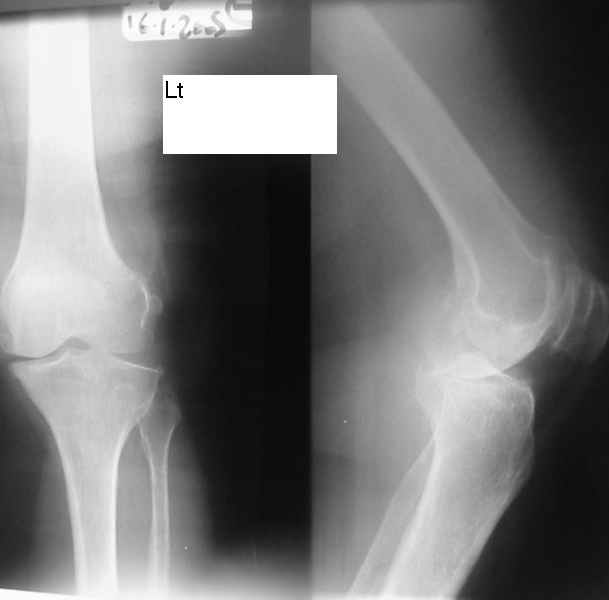

Dorogie Kollegy,Ko mne obratilas' bol'najia, ei 64 goda, ona stradaet ot dvuhstoronnego varusnogo gonoartroza, ei bila vipolnena Visokajia Ostotomjia goleny sprava 01.06.2004, zona osteotomii ne sroslas', plastina bila udalena 12.09.2004 (vidimo iz-za ee nestabilnosti), zona osteotomii tibia bila fixirovana 3-mjia shurupami. Seachas sylno bespokoyat boly v dvuh sustavah, hodit s trudom s pomoshyu Walker, a voobshe ona seachas na invalidnoi kolyaske. Podzkazite, pozhalusta, kak mozno ei pomoch' (snimky prilagayutsa)

U bol'nogo non-union osteotomii tibii. V vozraste 64 let, sdelal bi sleduiezhee:

1. I predpochel bi ego: Total Knee Arthroplasty. Nuzhen budet Revision ( Long stem) tibial Component.

2. Ne sovetuiu delat' geroicheskix postumkov v otnoshenii Non union. Tut est' mnogo problem, ved' esteotomia provedena ne pravili'no s tochki zrenia deformazii. Orientazia ploskosto kollennogo sustava xotia ne ploxa v sagital'noii ploskosti, no vo frontl'noi idet sil;noie otklonenie narozhu i vniz. A nam tida ne nado.